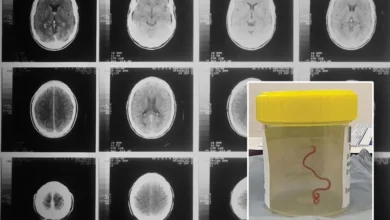

Αποκάλυψη σοκ για τον Ρόμπερτ Κένεντι Τζούνιορ: «Σκουλήκι έφαγε μέρος του εγκεφάλου του!»

Στην αποκάλυψη ότι ένα σκουλήκι έφαγε ένα μέρος του εγκεφάλου του Ρόμπερτ Κένεντι Τζούνιορ, ανιψιού του JFK και υποψήφιου για…

Σοκ: Αφαίρεσαν ζωντανό σκουλήκι από τον εγκέφαλο ασθενούς! Τα συμπτώματα και η πρωτοφανής λοίμωξη

Οι γιατροί στο νοσοκομείο της Καμπέρα έμειναν έκπληκτοι όταν αφαίρεσαν ζωντανό ένα παρασιτικό σκουλήκι από τον εγκέφαλο 64χρονης γυναίκας Παρασιτικό…